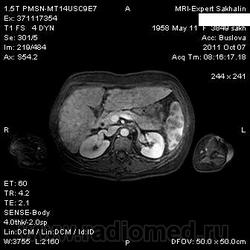

Постконтраст.

Добавила постконтраст.